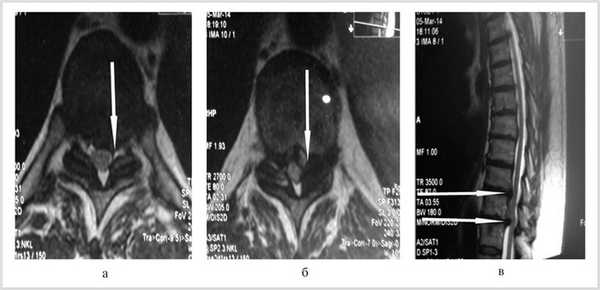

Больной обследован. При спондилографии грудного отдела позвоночника выявлен остеохондроз Th III —Th IV , II период, Th VIII —Th XII III период; данные MPT грудного отдела позвоночника: грыжи межпозвонковых дисков Th III —Th IV , Th IX —Th X , Th X —Th XI (рис. 1). При электронейромиографии нижних конечностей обнаружены выраженные изменения по аксональному типу в левом и правом малоберцовом нервах.

Рис. 1. Магнитно-резонансные томограммы грудного отдела позвоночника (Т1 режим): в аксиальной (а, б) и сагиттальной (в) плоскостях до операции.

Проведена МРТ (рис. 2): компрессия спинного мозга устранена. Больной переведен в неврологическое отделение для восстановительного лечения.

Рис. 2. Магнитно-резонансные томограммы грудного отдела позвоночника (Т1 режим): в аксиальной (а, б) и сагиттальной (в) плоскостях через 2 нед после операции.